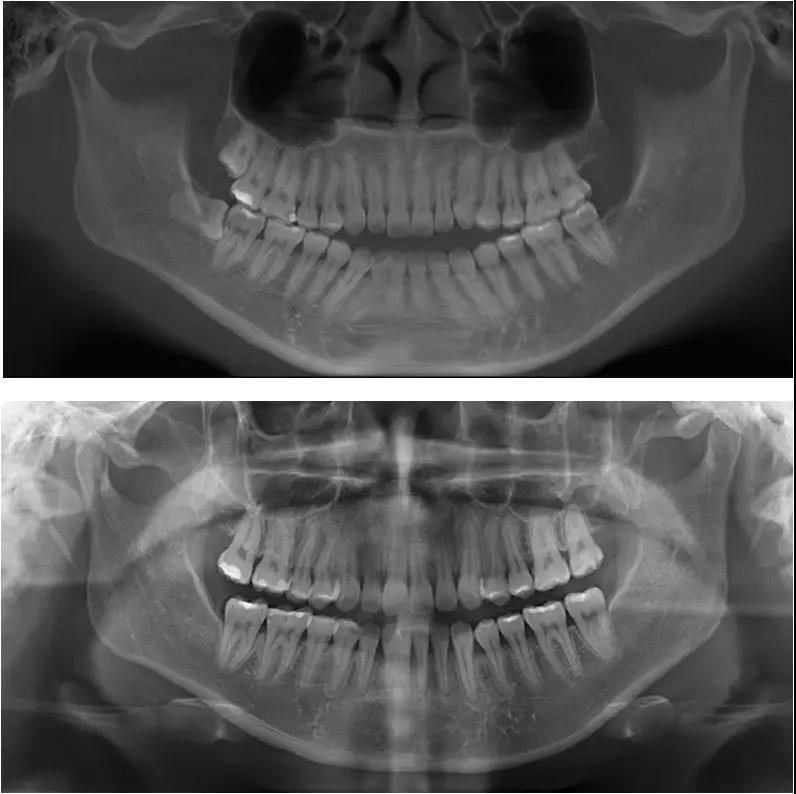

图17 治疗前后曲面体层片对比

术前曲面体层片